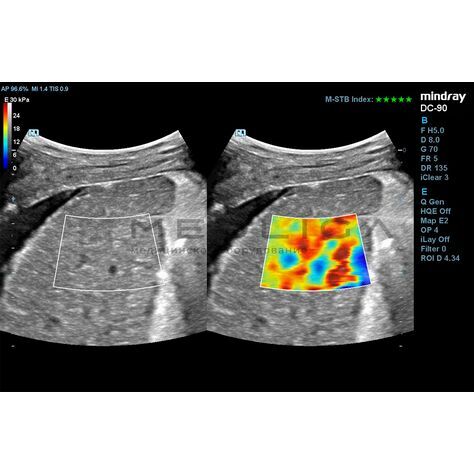

STE (Sound Touch Elastography)

STE интегрирована с эксклюзивной технологией Ultra-Wide Beam Tracking от Mindray для двумерной эластографии сдвиговой волной в реальном времени. Специализированные измерительные инструменты позволяют проводить количественный анализ модуля упругости с высокой точностью.